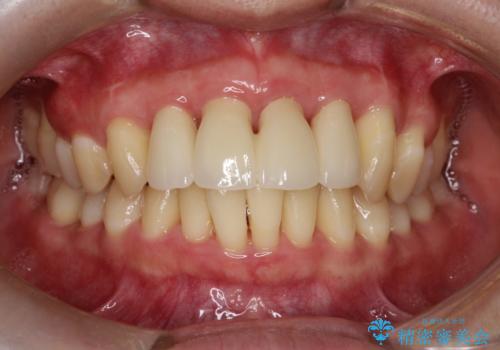

侵襲性歯周炎。前歯の歯周補綴

- 前歯がグラグラすることを主訴に来院されました。

再生治療後、歯周補綴を行っております。

歯周病が進行してしまった歯に対し、再生治療および歯周補綴を行うことで歯周組織の安定を得ることができました。